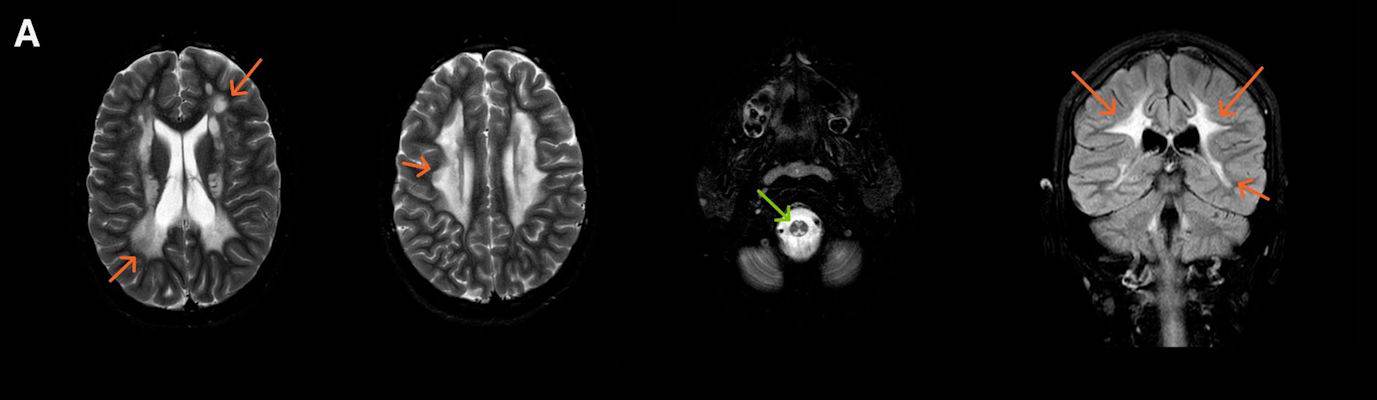

- A) Aksiyel T2A ve koronal T2A sekanslarda sentrum semiovale, korona radiata ve bazal ganglionlar düzeyinde bilateral frontoparietal derin periventriküler beyaz cevherde birleşme eğilimi gösteren hiperintens gliotik sinyal değişiklikleri (oklar) ve aksiyel T2A serilerde servikal spinal kordda posterior kolonda, lateral kesimlerde sinyal artımları (oklar) izlendi.

- LBSL, karakteristik radyolojik özelliklere sahiptir. MRG’de tipik olarak bilateral ve simetrik beyaz cevher sinyal değişiklikleri görülürken, subkortikal U lifleri, internal kapsülün posterior kolları, trigeminal sinir traktları, serebellum, korpus kallozumun spleniumu, medulla oblongata ve omurilikteki dorsal kolonlar ile lateral kortikospinal traktlar genellikle korunur.

- Etkilenen bölgelerde T1’de hipointens, T2/FLAIR’da hiperintens sinyal değişiklikleri izlenir. DWI’de lezyonların periferinde kısıtlı difüzyon görülebilir. MRS’de beyaz cevherde laktat artışı saptanabilir, ancak bu her hastada mevcut değildir.

- LBSL tanısında majör kriterler; subkortikal U lifleri korunmuş serebral beyaz cevher, servikal düzey dahil omurilik dorsal kolonları ve lateral kortikospinal traktlar, medulla oblongata piramitleri veya medial lemniskus dekusasyonu tutulumu iken; minör kriterler korpus kallozum spleniumu, internal kapsül posterior kolu, superior ve inferior serebellar pedinküller, trigeminal sinir traktları, mezensefalik trigeminal yollar, medulla oblongata anterior spinosebellar traktları ve serebellar beyaz cevherdeki sinyal değişiklikleridir.